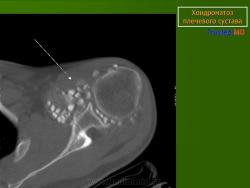

КСС. Хондроматоз внутрисуставной (синовиальный) 1. +

Хондроматоз внутрисуставной (синовиальный).

Хондроматоз

Хондроматоз внутрисуставной (синовиальный)

Хондроматоз суставов — хрящевая островковая метаплазия синовиальной оболочки

Синовиальный хондроматоз

Первичный синовиальный хондроматоз